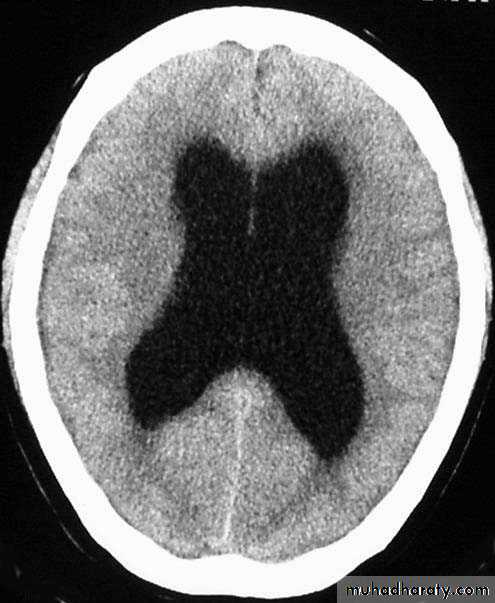

Normal Ventricles

Hydrocephalus